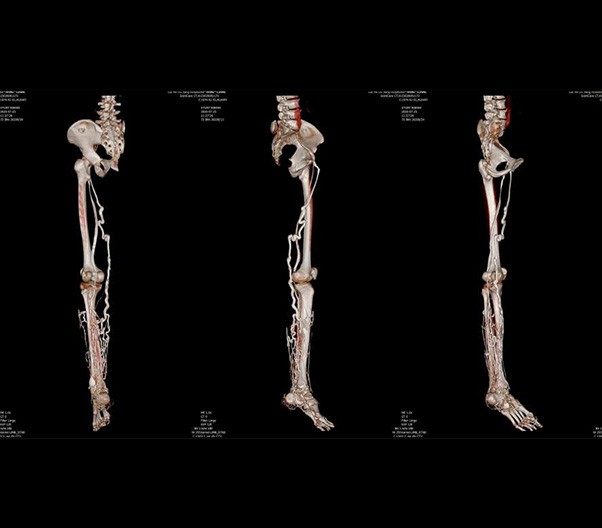

The 1024-pixel image matrix brings superior image clarity (0.6 mm slice thickness) and stimulates the early detection of small lesions, thus improving diagnostic reliance.

ScintCare CT 16 incorporates an entirely digital integrated ScintiStar detector, which was solely developed by MinFound, from material to the whole structure design, based on the technical know-how of our skilled scientific team. The system produces high-resolution images with a low radiation dose and an excellent signal-to-noise ratio.

NDI NanoDose Iteration Algorithm (NDI) is an innovative iterative technique for image reconstruction that takes full advantage of deep learning in anatomical structure in image space as well as model-driven iteration involving tube and detector in projection space, with the aim to generate sharp and high-resolution images at the lowest possible dose.